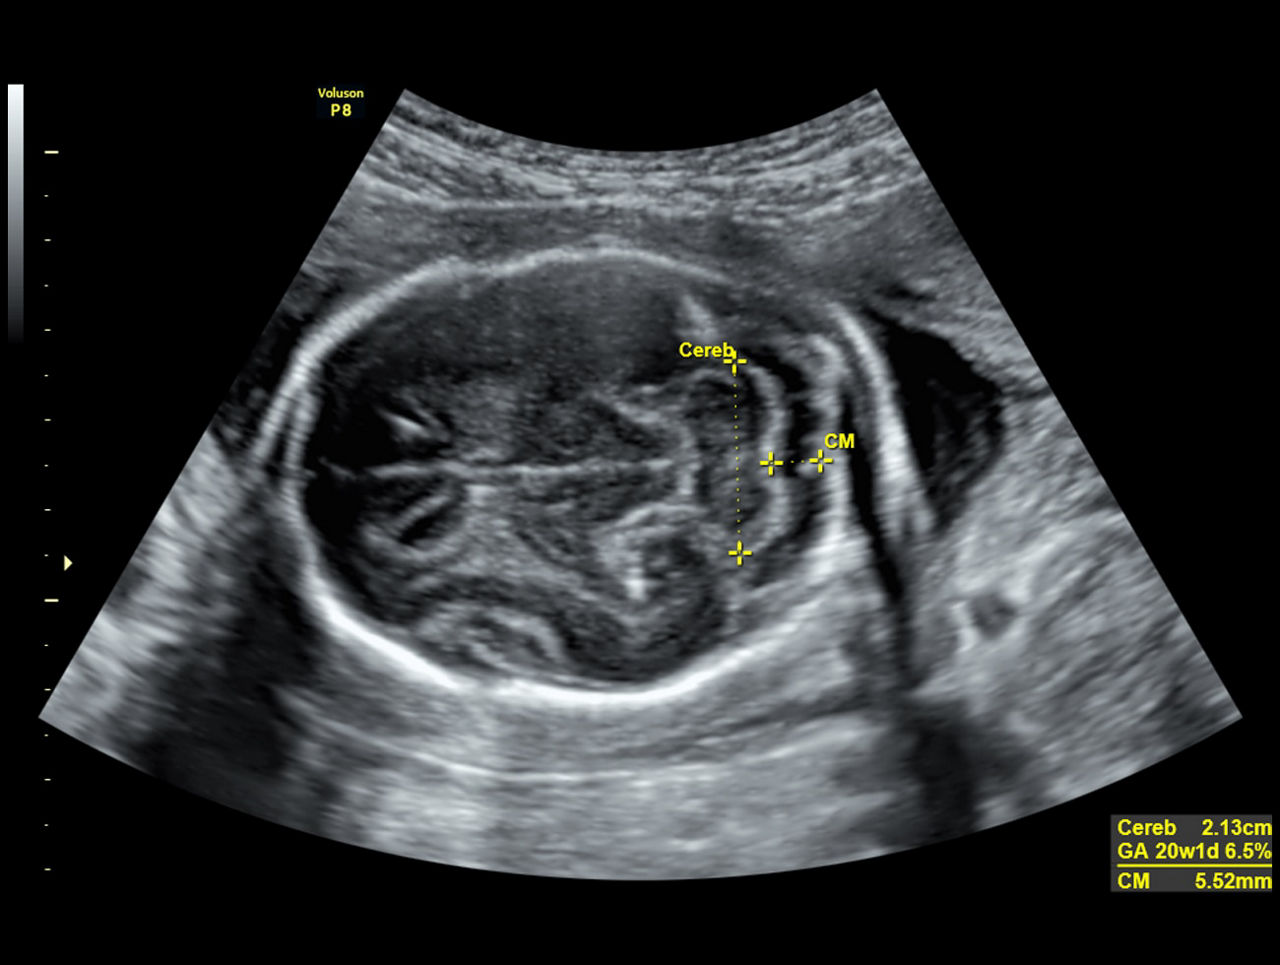

SonoBiometry

Reduce keystrokes with SonoBiometry – Semi-automated biometry measurements (BPD, HC, AC, FL, HL, Vp, CM, Cereb, FHR).